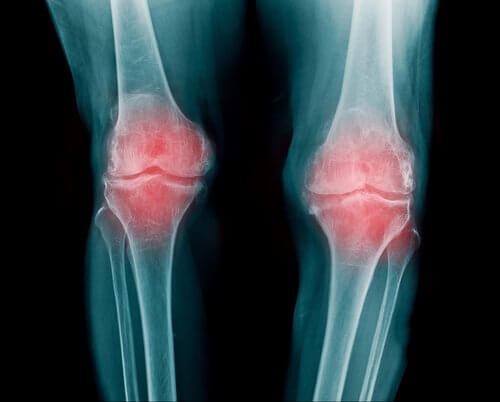

Drętwienie kończyn a kondycja stawów

Stawy to elementy układu kostno-szkieletowego, które są podatne na kontuzje, uszkodzenia i różne choroby. Bardzo często jednym z pierwszych objawów problemu jest drętwienie kończyn, a konkretniej dłoni, stóp, ramion i nóg.

Gdy jednak drętwienie kończyn staje się problemem przewlekłym i zaczyna negatywnie wpływać na jakość codziennego życia, należy niezwłocznie pójść do lekarza. Częste mrowienie może być objawem rozwijającej się choroby.